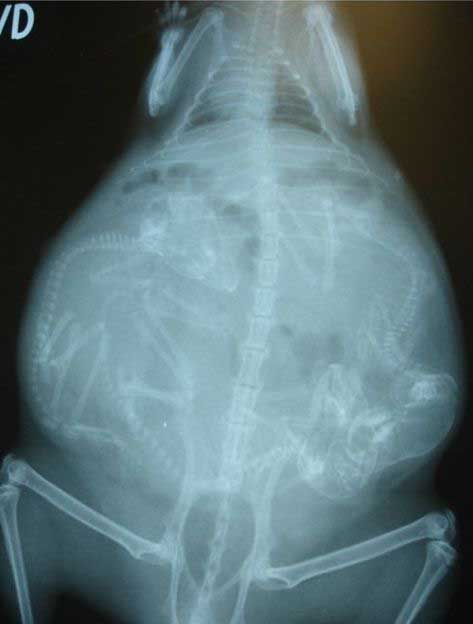

妊娠した様々な動物たちをレントゲン(X線)写真で見てみたギャラリー。サメ、ネズミ、犬、猫など。一度に複数の子供を出産する犬や猫などは特に怖い事に…。

4. イヌ